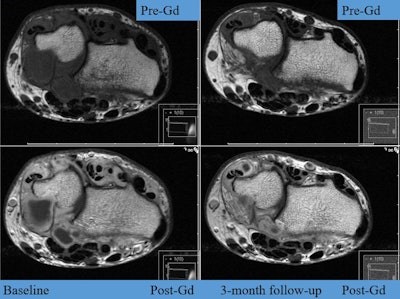

"The purpose of this follow-up study was to use MRI, which is reliable, objective, and more sensitive than x-ray, to make a secondary assessment of inflammatory activity and structural damage progression in the two study arms," Haavardsholm wrote in the press release. "If there really were a difference, we would expect to see it in the MRI results."

In the ultrasound arm, physicians stepped up treatment if indicated by the ultrasound score, overruling the disease activity score and swollen joint count. MRI of the dominant hand was performed six times and scored in chronological order by a blinded reader. After exclusions, 218 patients (ultrasound n = 116, conventional n = 102) had MRI at baseline and at one or more follow-up visits.

A combined inflammation score was computed by normalized summation of the synovitis, tenosynovitis, and bone marrow edema scores. A combined damage score was computed by normalized summation of the erosion and joint space narrowing scores.

The proportion of patients in each treatment arm with MRI erosive progression after two years was calculated, using the smallest detectable change (0.61) as the cutoff.